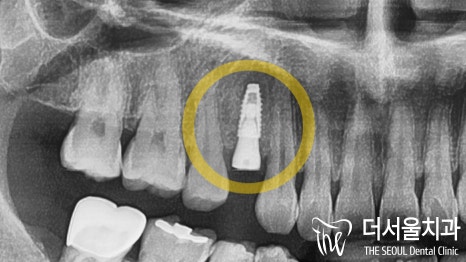

30대 임플란트 의 마지막 과정입니다.

전과는 달리 검게 썩어 있던 곳들이

모두 개선되어 있는 것을 확인할 수 있습니다.

다행히 골융합은 물론이며

크라운의 형태 또한

주변 인접치들과 잘 어울리는 모습으로

알맞게 제작된 것이 관찰되네요.